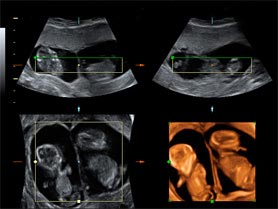

Ecografía para el diagnóstico del embarazo gemelar

Permite saber cuántos bebés hay, si comparten la placenta y/o la bolsa

La ecografía es el mejor método diagnóstico no sólo para identificar una gestación gemelar, sino también para catalogarla y especificar su corionicidad (número de placentas) y su amniocidad (número de bolsas).

El indicador más fiable de bicorionicidad (dos placentas) es la visualización de dos placentas separadas. Este signo es de gran utilidad en gestaciones muy precoces, ya que posteriormente estas placentas pueden fusionarse.

Si sólo se visualiza una placenta, la mejor forma de establecer si es bicoriónica es la presencia del signo "Lambda" o de "Twin Peak". Este signo se trata de una proyección triangular del tejido coriónico que se extiende desde las dos placentas hasta la membrana interfetal. Este signo es útil al principio de la gestación ya que después de la semana 20 se hace menos prominente y suele desaparecer.

El signo ecográfico que identifica la gestación monocorial (una sola placenta) es el signo de la "T". Se refiere al ángulo de 90º que forma la fina membrana interfetal con la placenta. La presencia del signo "T" tiene una sensibilidad muy alta para el diagnóstico de la gestación monocorial.